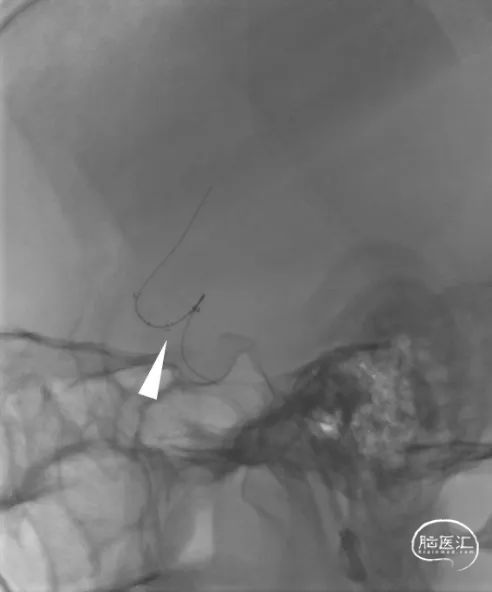

20230502 AM 11:08 全麻赛诺神畅 079-95 APEX TRA DA+130 SIM 2 GC+ Catalyst 6。

20230502 全麻 Catalyst 6+ Synchro 2+赛诺神畅 Neuro LPS™ 1.5×10。

20230502 赛诺神畅 Neuro LPS™低压球囊扩张。

20230506 AM 09:50 MRA。

20230420

20230506

20230506 HR-MRA VISTA+PD+VISTA+C。